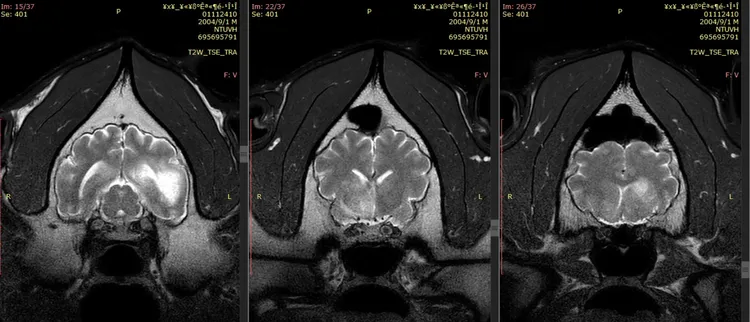

團團在上周六(10/22)已進行第2次MRI(磁振造影)檢查,今園方也公布結果,坦言團團「病程進展快速」,腦部惡性腫瘤的機率也大幅提高,不過未能進行侵入性切片檢查,故無法百分之百確認。

動物園表示,團團第2次MRI影像顯示腦部病變除既有的病灶外,區域明顯擴大且出現腫塊效應,團團這次檢查對麻醉反應、甦醒恢復時間也都延長,考量近期種種臨床表現,園方也宣布「不再對團團進行麻醉或侵入性檢查」,將以維護動物福祉為優先,採舒緩照護方式照顧。